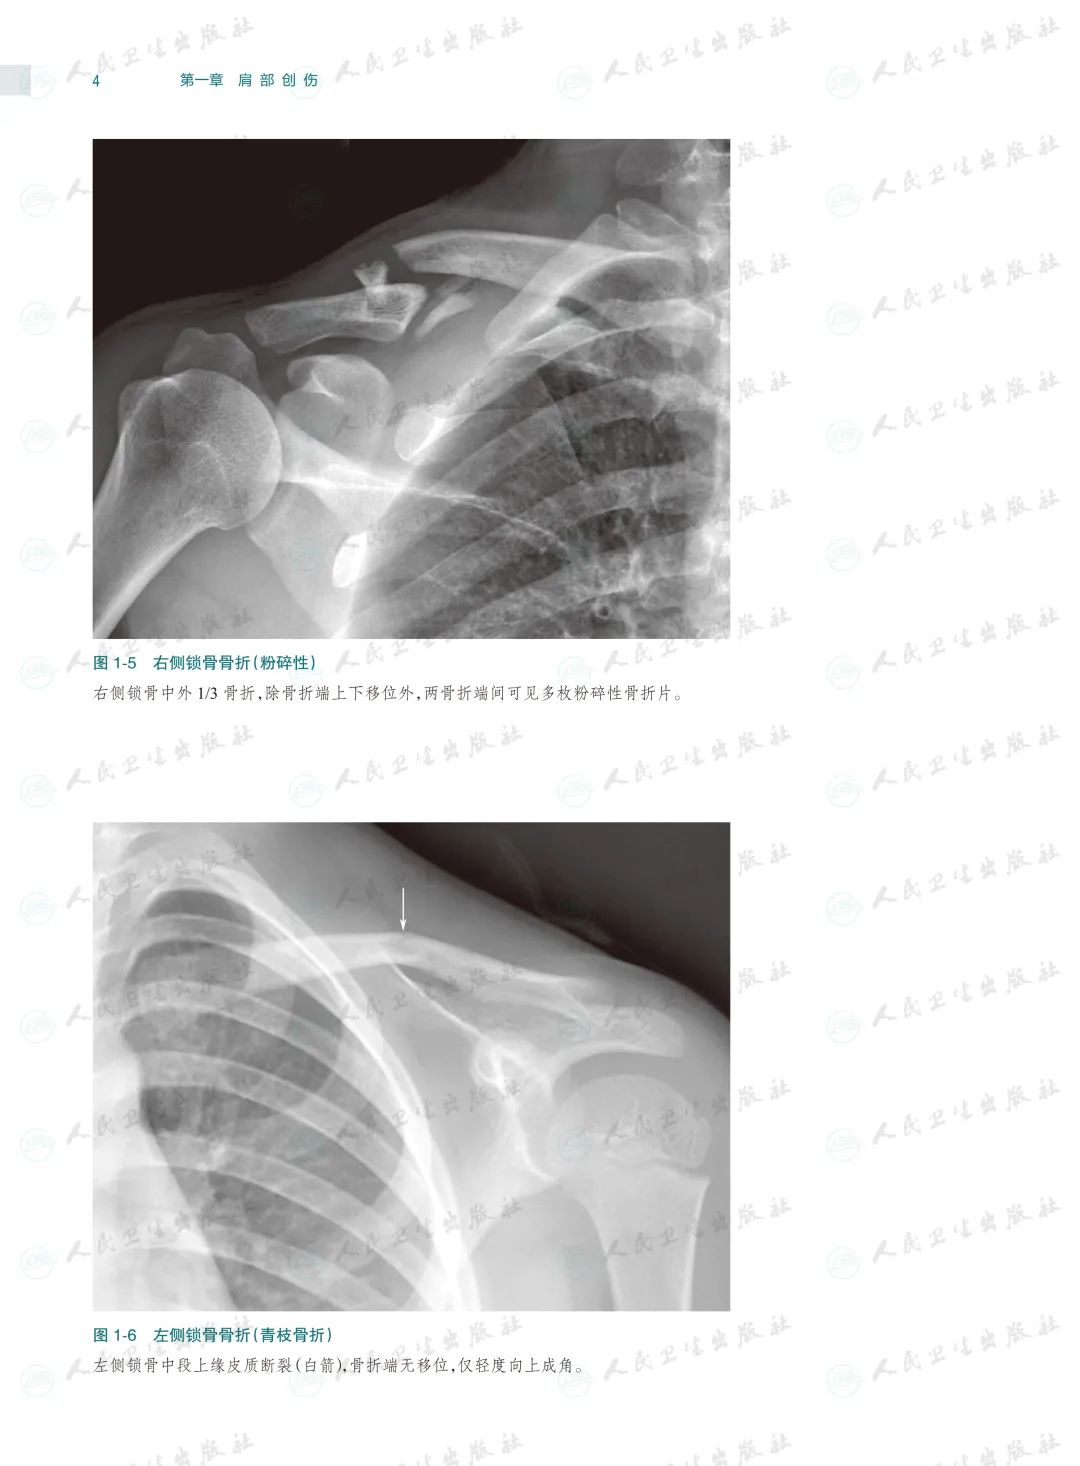

骨关节创伤是骨科临床常见病,X线检查是其最基本和最常用的检查方法。本书以临床典型病例X线检查资料为素材编写,已是第4版了,一直以来本书都因为其实用性而深受读者的喜爱,本次修订根据近几年骨关节创伤领域的#新进展,对目录进行了重新编排、对过时内容进行了修改、对清晰度和对比度欠佳的图片进行了替换,同时还充实了10多个病种的病例图片,并新增了常见骨关节创伤后遗症及并发症章节。

本书以图片展示为主,内容丰富,几乎包括了除头面部以外各个部位的骨关节创伤类型,图片清晰且有详细文字注解,每一章节的创伤类型、诊断要点和鉴别诊断均作了简要叙述。由于图片都是来自作者日常工作的资料积累,因此实用性较强,是一本不可多得的参考书。

本书在第3版基础上修订而成,是一本系统全面介绍骨关节创伤X线诊断的图谱专著。全书共十六章,前十五章每章基本按创伤类型、诊断要点和鉴别诊断体例编写,最后一章介绍常见骨关节创伤后遗症及并发症。书中共选用1270幅X线照片图,约760个病例,所选图片和病例均具有代表性,可使读者对各部位、各类型的骨关节创伤及其后遗症和并发症有进一步认识,从而提高诊断水平。本书主要供骨科医生、影像科医生及医学院校相应专业的学生使用。